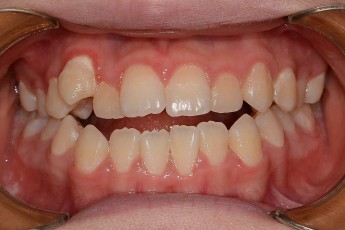

Before

After